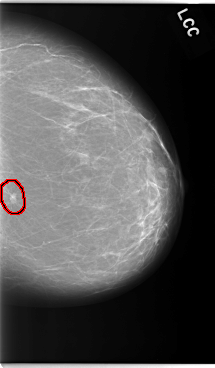

C_0042_1.LEFT_CC

LEFT_CC LINES 5880 PIXELS_PER_LINE 3432 BITS_PER_PIXEL 12 RESOLUTION 50 OVERLAY

FILE: C_0042_1.LEFT_CC.OVERLAY

TOTAL_ABNORMALITIES 1

ABNORMALITY 1

LESION_TYPE MASS SHAPE IRREGULAR MARGINS SPICULATED

ASSESSMENT 5

SUBTLETY 5

PATHOLOGY MALIGNANT

TOTAL_OUTLINES 1

BOUNDARY